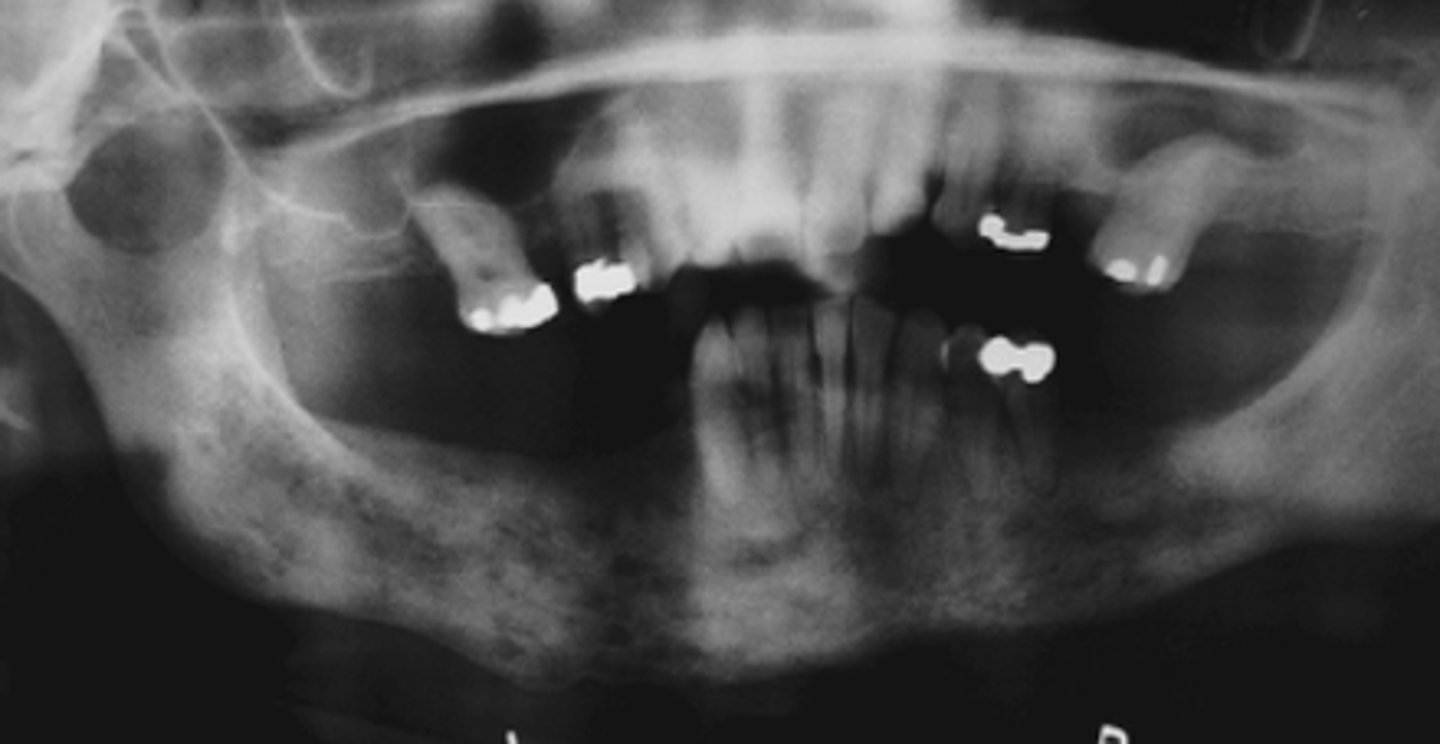

What is osteomyelitis due to?

Hypovascularity

Which gender is more affected by osteomyelitis in the mandible?

Men

What indicates osteomyelitis if borders are irregular?

Choose osteomyelitis

What is sequestration in chronic osteomyelitis?

Necrotic bony islands

What develops during chronic osteomyelitis?

Sinus tract